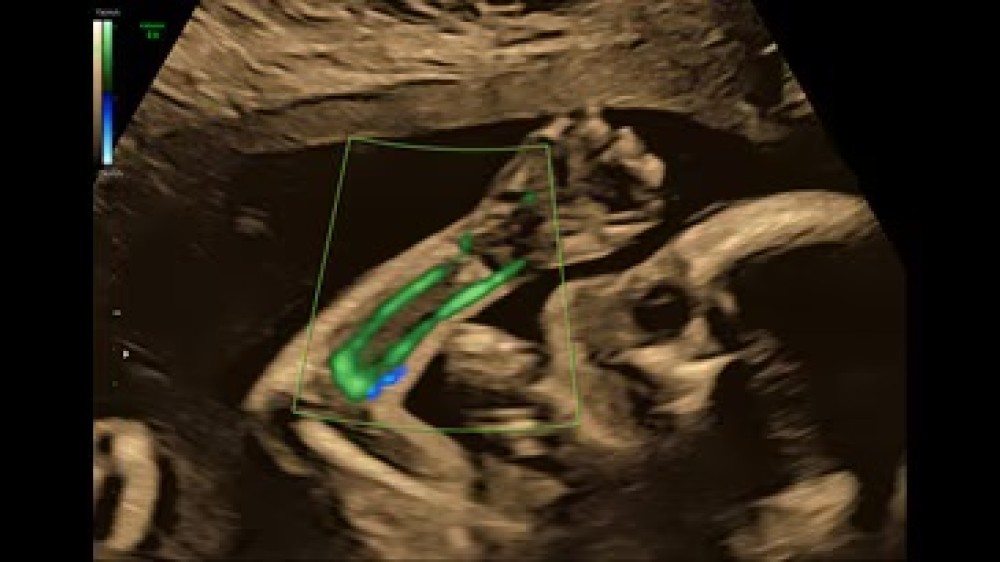

Voluson E6 GE Healthcare-in orta-yüksək səviyyəli ultrasəs cihazıdır və əsasən qadın sağlamlığı, obstetrik və ginekoloji müayinələr üçün nəzərdə tutulub. Sistem Radiance System Architecture üzərində qurulub və bu, yüksək keyfiyyətli 2D və 3D/4D görüntüləmə, həmçinin Color Doppler funksiyasını təmin edir.

Voluson E6-in avtomatlaşdırılmış funksiyalarıergonomik dizaynı operatora iş axınını optimallaşdırmaq, müayinələri daha sürətli və səmərəli icra etmək imkanı verir. Sistem fetal inkişafın, plasentanın, ürək fəaliyyətinin və qadın reproduktiv sisteminin dəqiq qiymətləndirilməsi üçün nəzərdə tutulmuşdur, eyni zamanda gündəlik klinik iş yükünü asanlaşdırır.